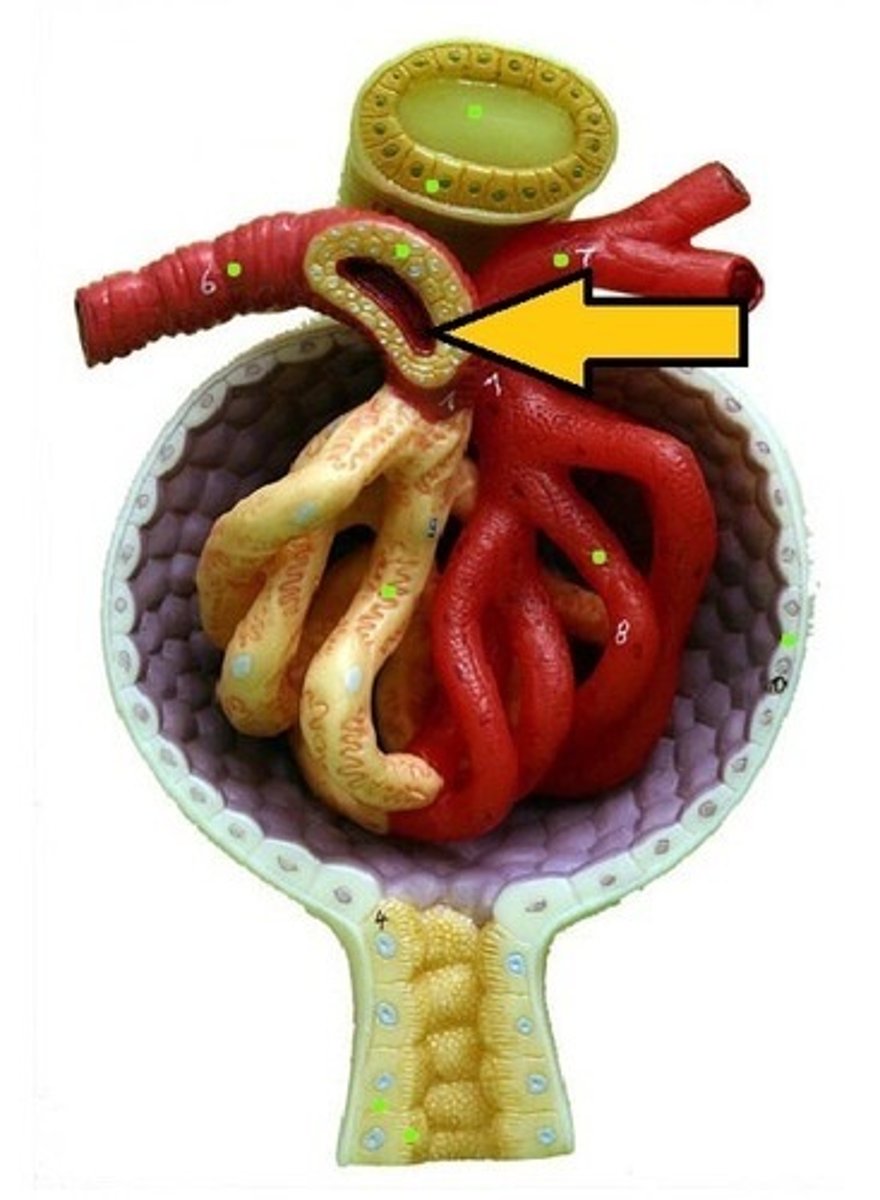

juxtaglomerular apparatus

Bowman's capsule / glomerular capsule

macula densa cells

cells

juxtaglomerular cells

cells

podocytes

cells

capsular space

the cavity

renal corpuscle